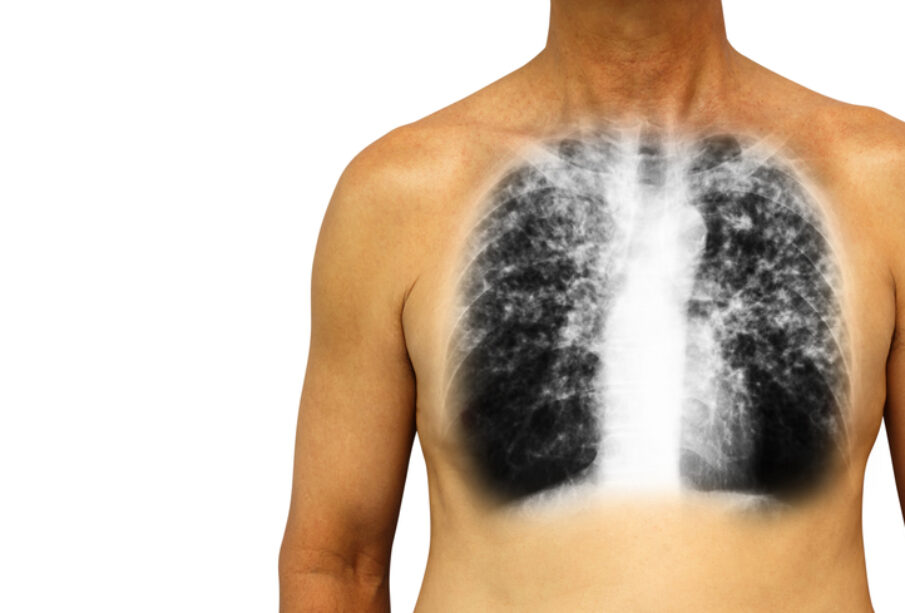

Απεικονιστικός έλεγχος πνευμόνων

- Ακτινογραφία θώρακα για την ανάδειξη λεπτών γραμμών μέσα στους πνεύμονες